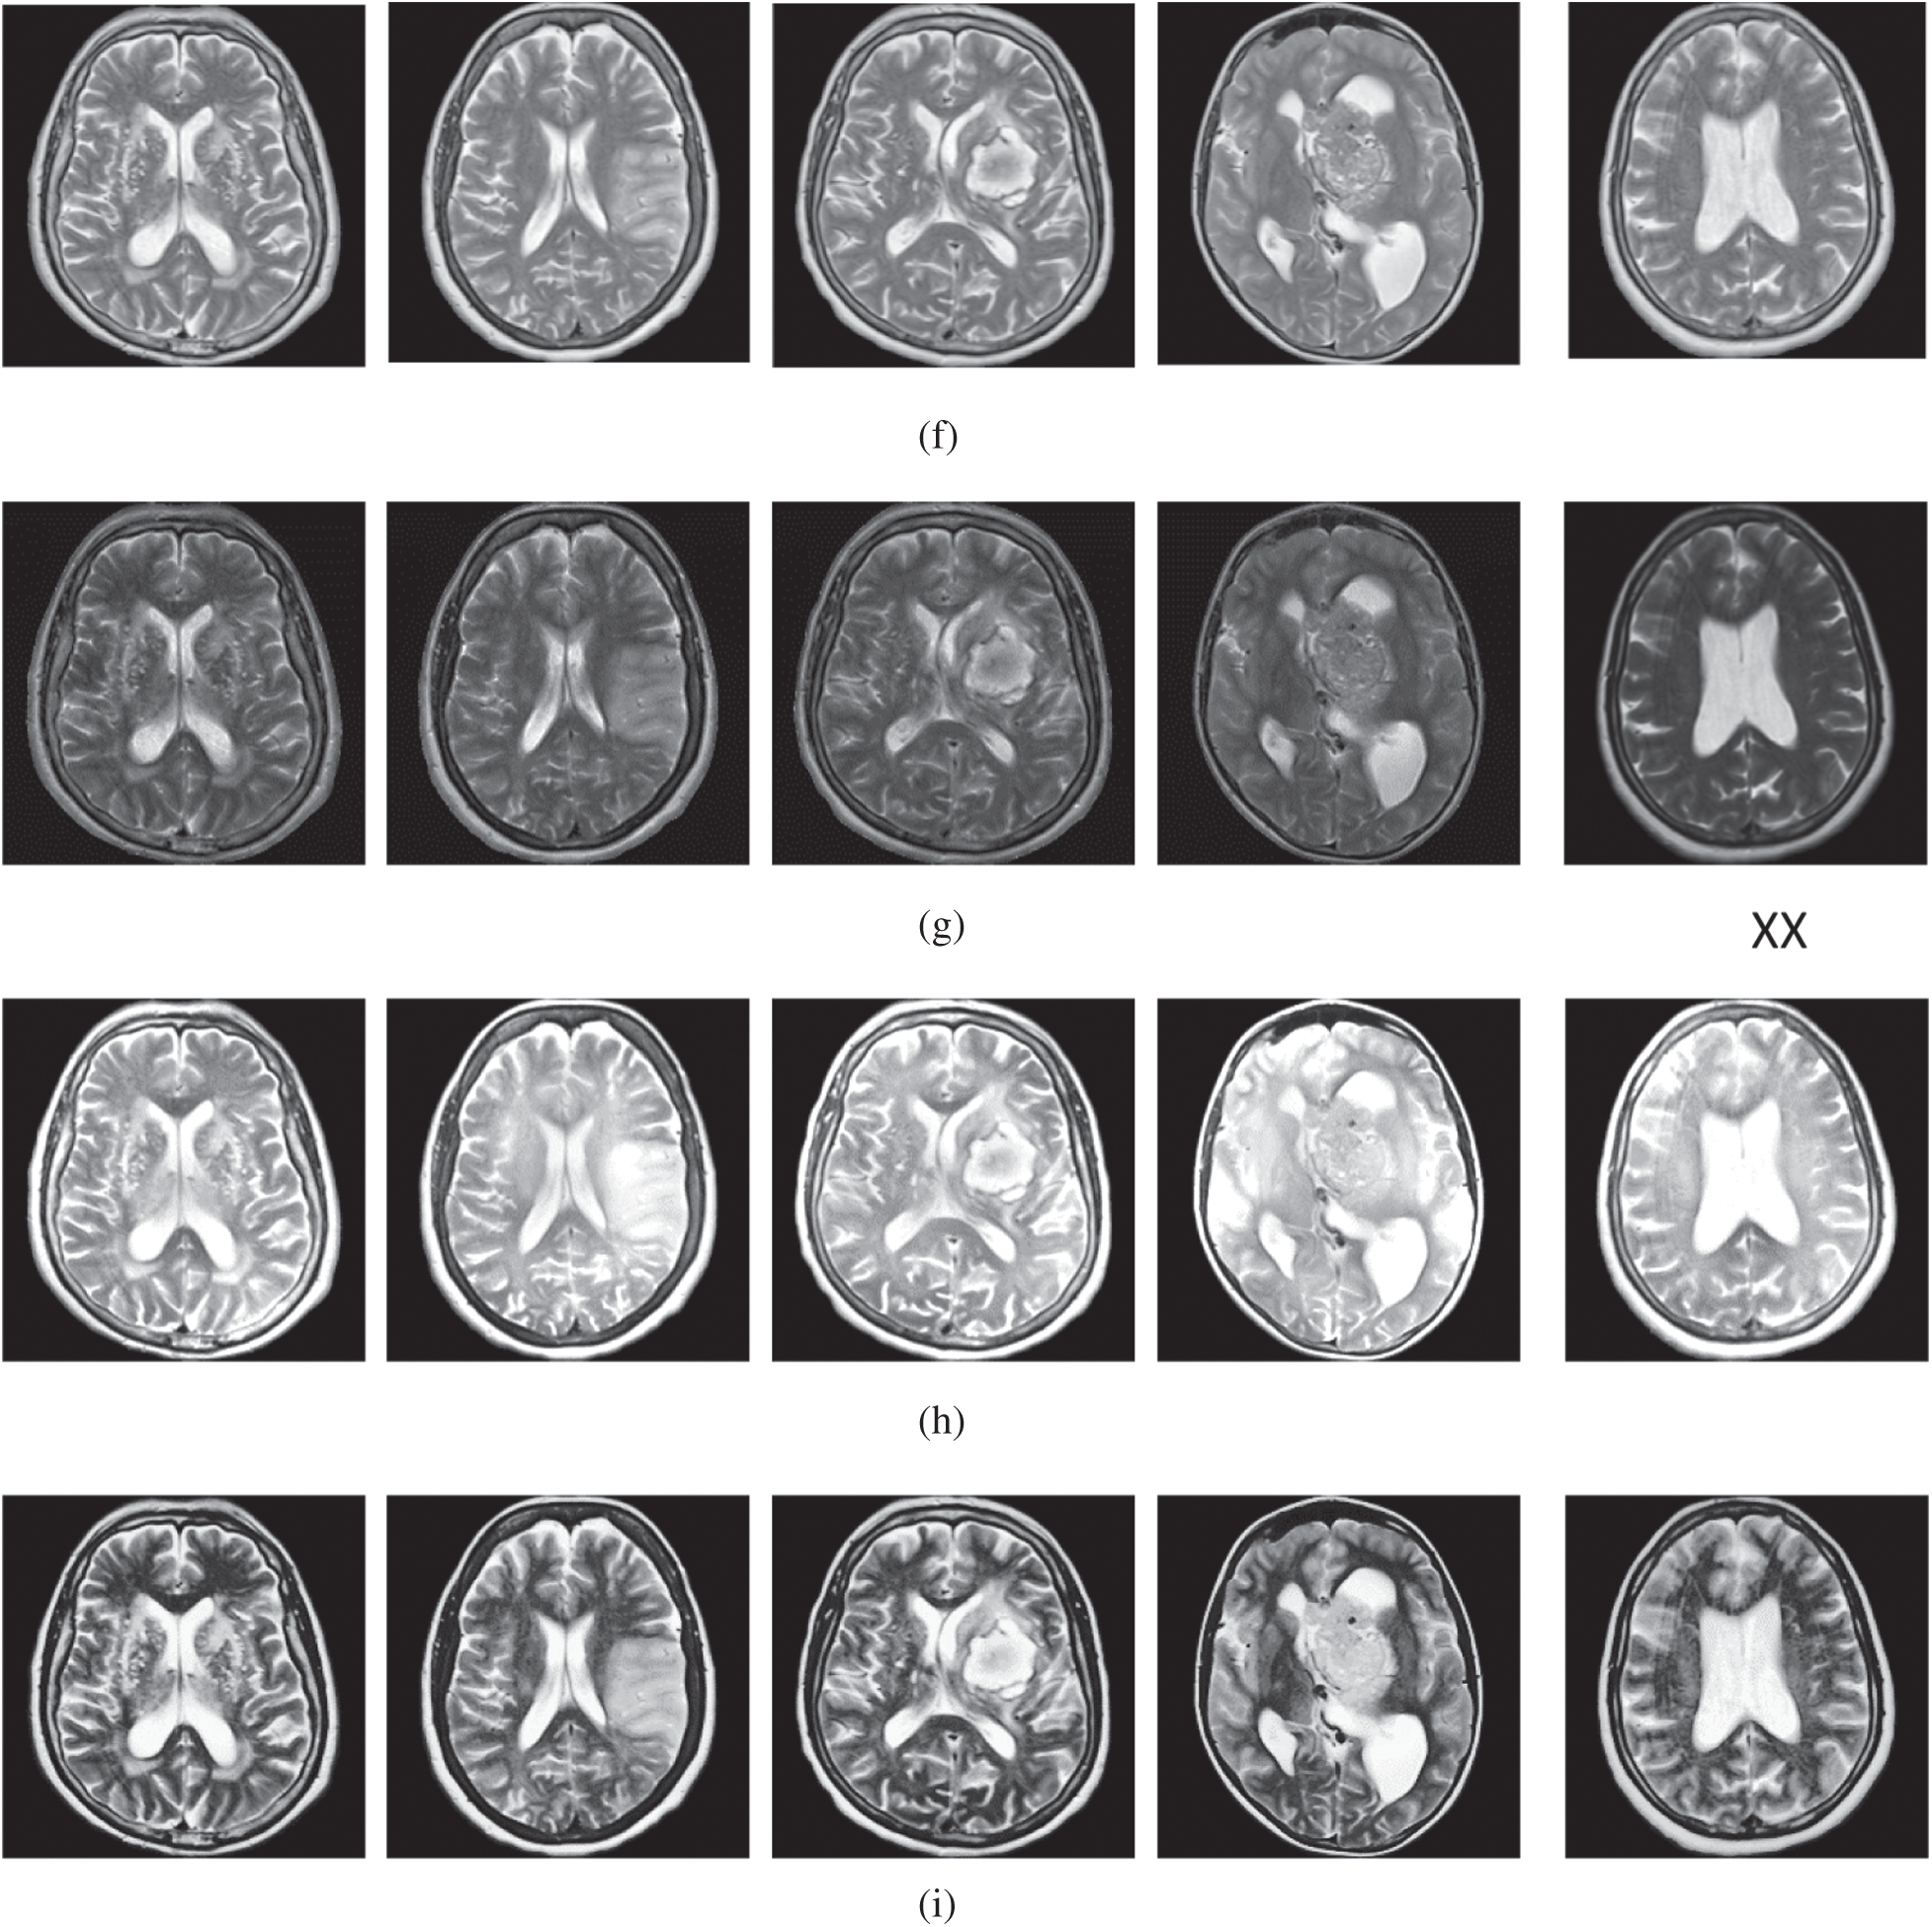

The qualitative results are illustrated in Fig. 3 for brain MRI; in Fig. 4 for lung CT, and in Fig. 5 for kidney MRI. As shown in the figures, all of the images have different trends with the dark and bright areas. It could be seen that the Histogram Equalization (b), Fu et al. [11] (f), and Zhang et al. [12] (h) methods produce over-enhanced images, while the proposed method produces natural appearance by enhancing the dark areas and maintaining the bright areas of input images. Overall, when we look at the input images and its enhanced images, the brightness of the fine details increases compared to the input images, irrespective of the content and application of the image. The brightening caused by the proposed FITE model makes the structures of the medical images well-defined and clear. The proposed FITE method introduces fair visual results for the weakly illuminated images. This is the contribution of fractional integral entropy in this study.

Figure 4: The lung CT enhancement results of the proposed and existing enhancement models. (a) Input Image, (b) histogram equalization, (c) Al-Shamasneh et al. [4], (d) Raghunandan et al. [7], (e) Al-Ameen et al. [10], (f) Fu et al. [11], (g) Li et al. [17], (h) Zhang et al. [12], (i) proposed FITE